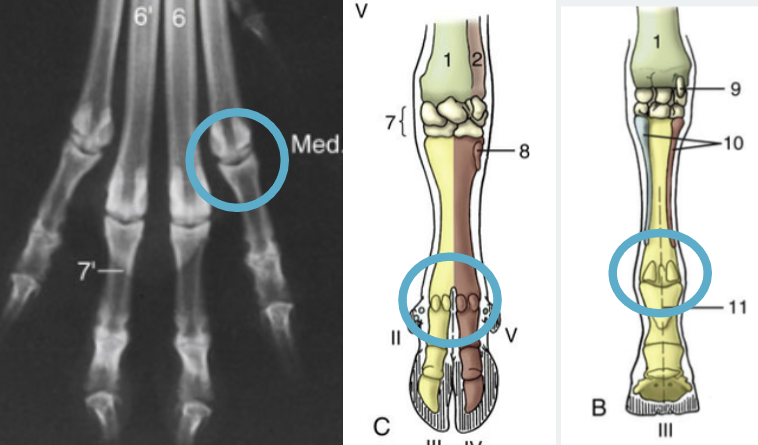

Which joint it shown?

Metacarpophalangeal Joint

Green arrow?

Proximal interphalangeal joint

Red arrow?

Distal interphalangeal Joint

Red circle?

Femorotibular Joint

Blue circle?

Femoropatellar joint